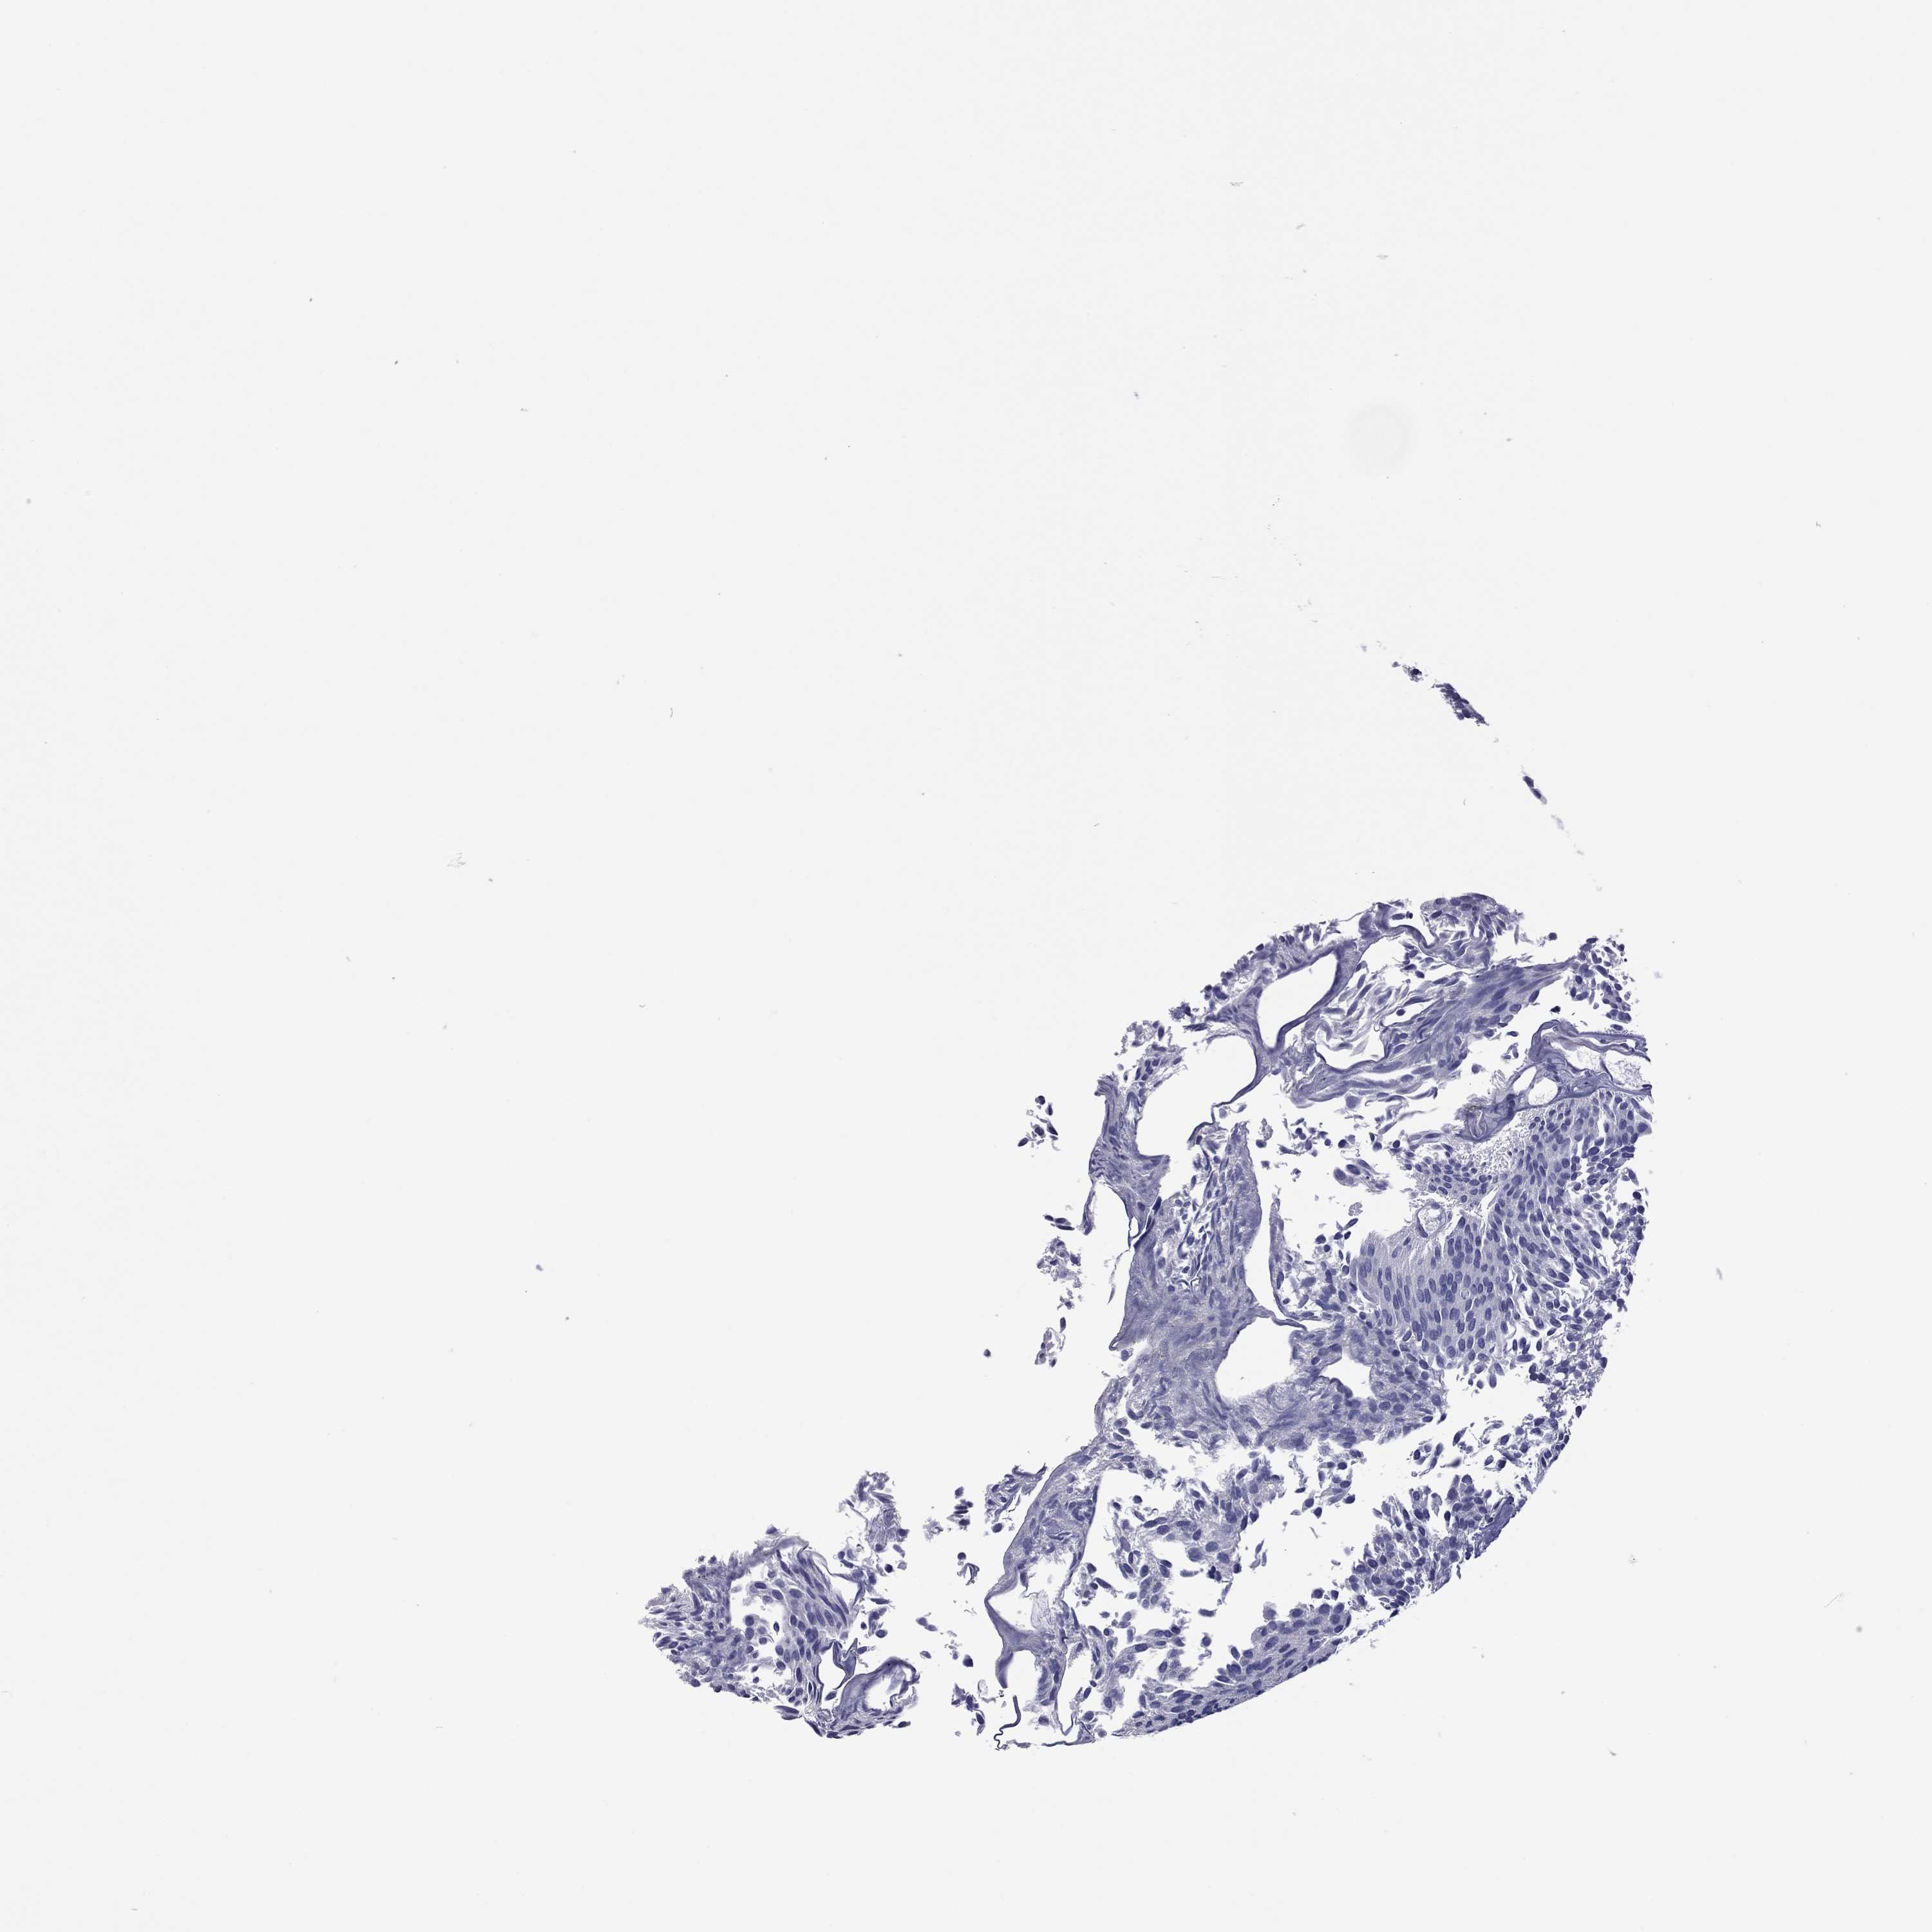

UROTHELIAL CANCER - Protein expressioni

A mouse-over function shows sample information and annotation data. Click on an image to view it in a full screen mode. Samples can be filtered based on level of antibody staining by selecting one or several of the following categories: high, medium, low and not detected. The assay and annotation is described here.

Note that samples used for immunohistochemistry by the Human Protein Atlas do not correspond to samples in the TCGA dataset.

Antibody stainingi

Antibody staining in the annotated cell types in the current human tissue is reported as not detected, low, medium, or high, based on conventional immunohistochemistry profiling in selected tissues. This score is based on the combination of the staining intensity and fraction of stained cells.

Each image is clickable and will lead to virtual microscopy that enables deeper exploration of all samples and also displays staining intensity scores, fraction scores and subcellular localization as well as patient and tissue information for each sample.

Antibody HPA077615

Staining

High

Medium

Low

Not detected

Intensity

Strong

Moderate

Weak

Negative

Quantity

>75%

75%-25%

<25%

None

Location

Nuclear

Cytoplasmic/membranous

Cytoplasmic/membranous,nuclear

Urothelial carcinoma, High grade

Urothelial carcinoma, Low grade